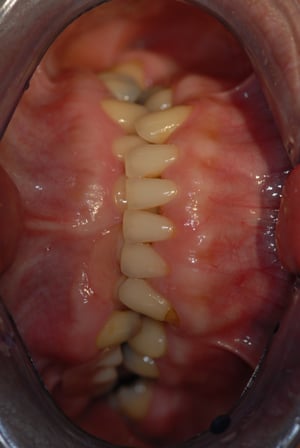

This is a middle age lady seeking to replace her missing teeth with dental implants. She also had a mild underbite. The lower jaw is only mildly longer than the upper jaw.

However, over the years, she had developed a habit of posturing the lower jaw forward and that had resulted in the an underbite that appeared more severe than it really was. As with most skeletal jaw size discrepancies, the teeth compensated naturally. The lower teeth were tilted backwards towards the upper front teeth, in an attempt to maintain contact with the opposing teeth.

Without surgery to correct the underbite, restoration with dental implants can either be conforming to the pre-existing occlusion whereby the jaw is postured forward into a deep underbite. Such a conformative plan is most expedient as it is simply filling up the missing teeth with dental implants that will not change the jaw relations. However, doing so means forgoing the opportunity to achieve an improved Class I occlusion, where the upper teeth overlaps the lower teeth slightly.

A compromise plan was eventually undertaken. Orthodontic treatment was done to open the bite, align the teeth and tilt the upper front teeth out and lower front teeth back to achieve a positive overbite and overjet. By raising the bite, more space is created for placement of implant supported crowns. This increase in vertical dimension also created better facial proportions. Originally, with the lower jaw postured forward, the bite was over-closed, shortening the height of the lower third of the face. Opening up the bite increases the vertical dimension of the lower third giving a more natural proportion. (Due to regulations in Singapore, after photos cannot be included.)